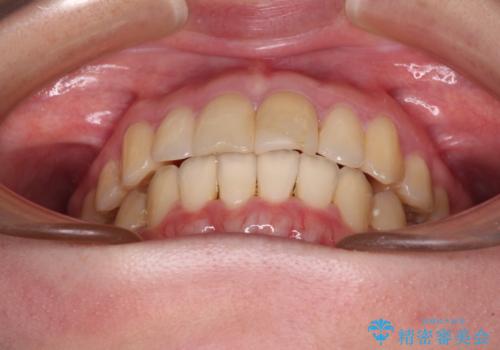

上下前歯のデコボコをきれいに インビザラインによる矯正治療

- 前歯の著しい叢生と前突感を気にして来院された患者様です。

叢生が強いため、事前に前歯をワイヤー矯正で速やかに叢生を解消し、その後はインビザラインにて矯正治療を行うこととしました。

ワイヤー矯正を併用したことで前歯の叢生を速やかに解消することができました。

一方口元の突出感を改善するために時間がかかり、2年超を要しましたが、満足のいく仕上がりとなりました。